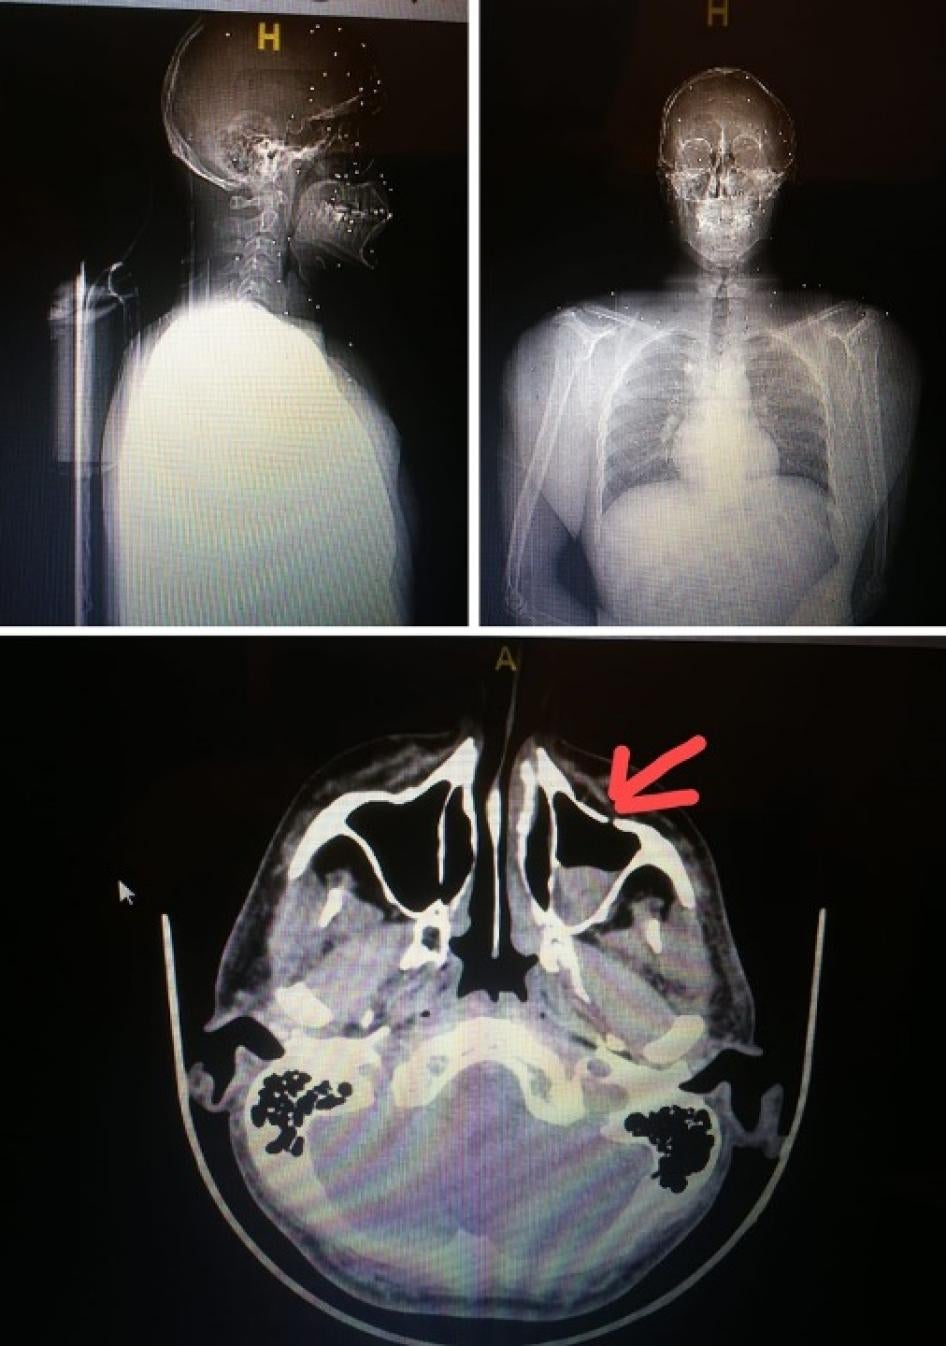

For the first time in Lebanon, Human Rights Watch documented several instances of Lebanese security forces using shotgun-fired metal pellets that wounded people. In some cases, security forces fired toward people’s upper bodies, including the head and face. Human Rights Watch reviewed medical records and X-rays, spoke to 3 victims and 4 doctors who treated them, and analyzed a pellet recovered from one person’s body, as well as a photograph of another. Additionally, the “White Shirts” doctors shared anonymized medical records of 13 patients seriously injured by the metal pellets.

Elie Saliba was hit with metal pellets. On the right, an x-ray shows a metal pellet that had embedded in his head. © 2020 Courtesy of Elie Saliba

Elie Saliba, a doctor who attended the protest, said that at around 5:15 p.m., security forces fired metal pellets from a pump-action weapon at him when he was between the former Virgin Megastore and the UFA Assurances Building near Martyrs’ Square. A metal pellet hit his shoulder. He then went to the roof of the Virgin Megastore building to film the security forces, including men in civilian clothes and soldiers, but he was shot at with metal pellets again, from a distance of about 20 meters. Although he was wearing a helmet, three metal pellets embedded in his head. He removed two on the spot. The next day, doctors removed the third one.

Dozens of pellets wounded this protester, puncturing their scalp and embedding under their sinus and in their eye. © 2020 Private

Dr. Nada Jabbour, president of the Lebanese Ophthalmological Society, said that 8 protesters had to undergo serious surgeries, and 3 lost their vision in 1 eye. The others, who did not require surgery, lost some vision due to their injuries, she said.

Another doctor shared the anonymized X-rays of a patient who was wounded by dozens of pellets. The doctor said that the number of pellets and the fact that they punctured the patient’s scalp indicate that security forces shot at the person’s face from a very short distance. The pellets embedded under the sinus in the skull and in the protester’s eye, the doctor said.

The same doctor treated another protester who was shot with a metal pellet in the neck. The doctor said that the pellet tore an artery in the neck, punctured the lung, and finally lodged in the protester’s spinal cord. The doctor said that, had the pellet been one millimeter closer to his spinal cord, the protester would have been permanently paralyzed.